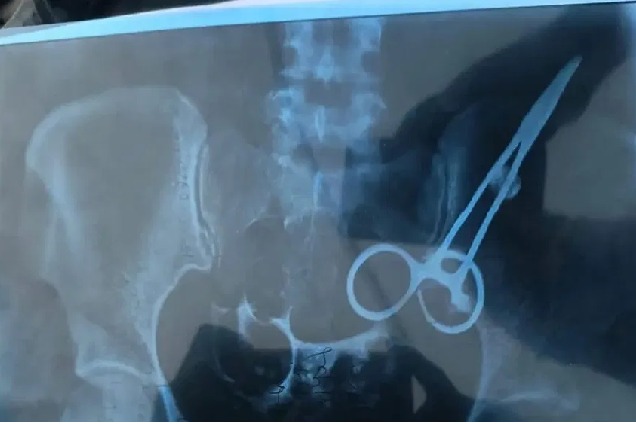

ఆపరేషన్ జరిగి అయిదేళ్లవుతున్న నొప్పి వెంటాడుతుండటంతో బాధితురాలు హైదరాబాద్లోని ఓ ఆసుపత్రిలో చేరింది. ఈ సందర్భంగా వైద్యులు ఆమెకు స్కానింగ్ నిర్వహించగా పొట్టలో కత్తెర ఉన్న విషయం బయటపడింది. దీంతో.. వైద్యులే నిర్ఘాంతపోయారు. మరోవైపు గతంలో మహిళకు ఆపరేషన్ చేసిన వైద్యుడిని నిలదీయగా ఆపరేషన్ ఖర్చులన్నీ తానే భరిస్తానంటూ కాళ్లబేరానికి దిగాడట. కాగా.. మహిళ కడుపులోని కత్తెరకు సంబంధించిన ఎక్స్రే చిత్రం ఒకటి నెట్టింట్లో తెగ వైరల్ అవుతోంది.